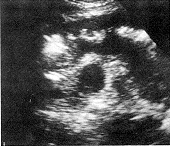

按照小肠肿瘤的超声图像分型〔7〕,本组21例转移性小肠肿瘤中19例均属壁厚型。肿瘤大体形态和长、短轴切面为受累肠壁增厚分别显示为假肾和靶环征(图1.2)。厚度范围0.8~2.0cm,长度范围3.0~7.0cm;2例长度>10cm分别为鼻咽部恶性淋巴瘤和白血病远端小肠侵犯,沿肠壁长轴浸润呈均匀低回声区(图3)。2例属腔外肿块型。11例为卵巢癌腹膜种植性转移连同小肠襻与壁层腹膜之间Φ3.0cm中等强回声型肿块并有多量腹水(图4)。另1例为睾丸精原细胞瘤小肠转移,相当于远端小肠与膀胱之间见Φ6.0cm中等回声实性肿块伴边缘肠腔强回声及膀胱内游离气体,提示:小肠外生型肿瘤侵犯膀胱并有内瘘形成,X线气钡双重对比造影后患者排出白色钡剂尿液(图5,6)。

沿肠壁长轴广泛浸润 卵巢癌侵犯邻近小肠

并见Φ3.0cm中等强回声型肿块

图3 白血病小肠侵犯 图4 腔外肿块型转移性小肠肿瘤